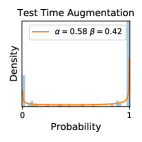

5.1 Distribution of Uncertainty Scores

Distribution of Uncertainty Scores Across Different Severity Levels As explained in Section 3, each uncertainty metric essentially defines an order/ranking among the data points. We conducted an analysis to better understand what data will be assigned high uncertainty under a particular uncertainty metric . Picking out the highest ranked data points (), we calculated the ratio of data points from each SL. Figure 4 summarizes the results as box plots for the Kaggle-DR and the Messidor-2 datasets; additional detailed statistics can be found in Table S.1 in the supplementary materials. From the plot and table, SL1 & SL2 examples account for a higher proportion among the top-ranked uncertain examples across the three ensemble methods. This finding matches our intuition that incipient disease examples (SL1 & SL2) are more likely to be considered uncertain by ensemble methods due to their ambiguity.

In contrast, the MC-dropout method showed the worst overall performance among the three, as it can be seen from the high ratios of SL0 examples among the uncertain negatives in Figure 4. The histograms in Figure 2 provides another perspective to look into the phenomenon, where a decent proportion of MC-dropout model’s predictions on SL0 inputs entailed low confidence (far from 0 or 1), which from another angle explained why MC-dropout was less specific in terms of lower FNP; many no-DR inputs (i.e. SL0) were erroneously assigned high uncertainty by MC-dropout models.

It is still an open question why the evaluated MC-dropout networks signaled relatively high uncertainty on SL0 & SL3 & SL4 data that are less likely to be ambiguous. We conjecture that much of the “uncertainty” indicated by disagreement among test-time dropout samples actually reflects the stochastic nature of dropout networks rather than the real decision uncertainty associated with the data. It is worth noting that the MC-dropout model we evaluated was not weak per se; they all achieved above Area Under Curve (AUC) scores on test sets. The weakness of individual test-time samples (which explains their low-confidence predictions on SL0 & SL3 & SL4) might have been hidden when they are aggregated into an ensemble—a well-known advantage of ensemble learning. Our results suggested that the uncertainty information given by implicit ensemble methods such as MC-dropout and TTA might not be as reliable as that from explicit ensemble approaches (e.g., stacking ensembles). Similar findings on MC-dropout can be found in some previous papers [1].